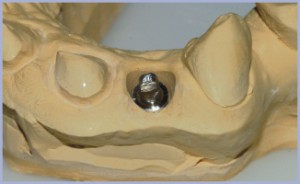

Nella stessa seduta è stato quindi possibile rilevare un’impronta con transfer Standard diametro 4,1 mm (figg. 16, 17).

In considerazione dell’alta valenza estetica della zona si è optato per la realizzazione di un moncone individualizzato in titanio-zirconia (fig. 18) con l’ausilio della tecnica CAD-CAM Sirona.

Per queste motivazioni il primo passaggio è stato quello di adattare un moncone diametro 4,1 mm dritto Standard modificandone adeguatamente la parte emersa (figg. 19, 20) che è divenuta l’interfaccia per l’alloggiamento della porzione in zirconia individualizzata.

Il modello in gesso con l’interfaccia in titanio e stato scansionato per la progettazione al CAD (figg. 21, 22, 23, 24, 25).